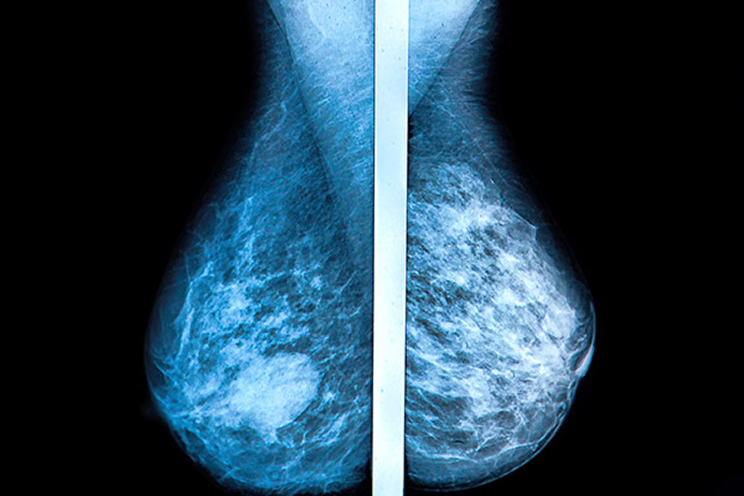

Digital breast tomosynthesis (DBT) is an advanced form of mammography that captures multiple low-dose X-ray images of the breast from different angles. These slices are reconstructed into a 3D image, providing a clearer view of internal structures compared to traditional 2D mammograms.

This 3D imaging approach minimizes the issue of tissue overlap, which often obscures small tumors or lesions in 2D scans. DBT significantly improves cancer detection rates, particularly in women with dense breast tissue.